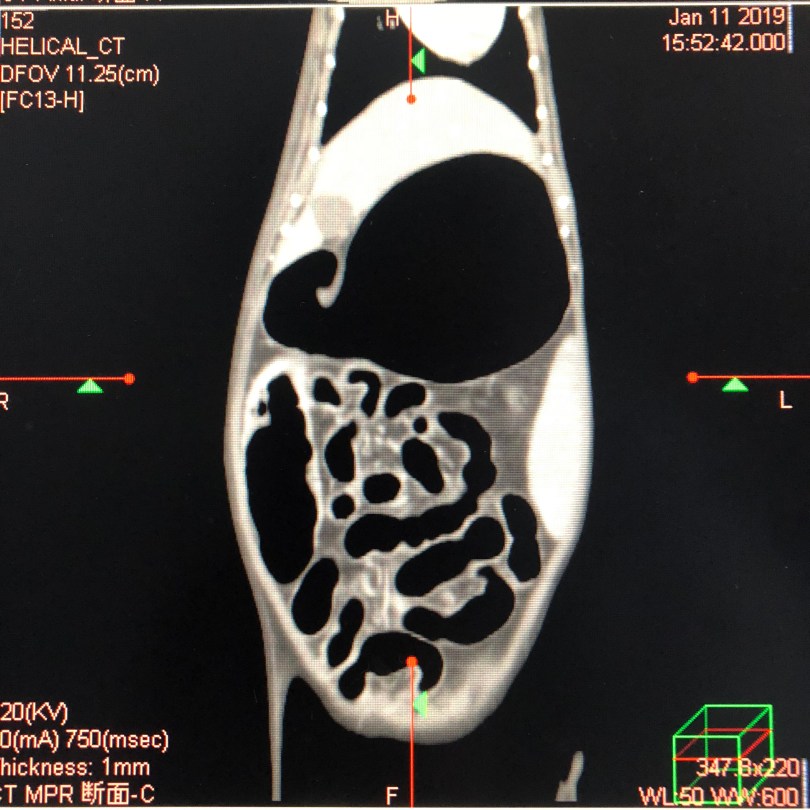

異物などを誤って食べてしまい腸閉塞を起こした猫さんのCT画像です。異物によって腸閉塞を起こした腸は、腸全体に渡り、動きが悪くなり、腸ガスが溜まりお腹が膨れてきます。と同時に、嘔吐や下痢も併発し始めていき、ご飯は一切食べなくなります。また猫さんがたくさんの回数吐くことで膵炎や腸炎、さらには胆管炎なども合併症として起こしてしまうケースも珍しくはありません。このような重篤な状況に陥ってしまうと、原因となっている異物自体を取り除かなければ助からないこともあります。つまり外科的に異物を摘出するということです。

当院では異物自体を迅速に発見し、最短距離で手術を終わらせるためにCT検査を実施しています。CT検査が行えれる医療機関は異物が疑われる場合、CT検査を行うことはマストだと思います。この件についてはいつか触れたいと思いますが、当院獣医師主任である児玉が学会発表をしており、CT検査を実施することで異物の発見率はほぼ100%であるという報告までさせて頂いています。「そんなのあたりまえだろ」と思われててもおかしくない内容ではありますが、これまで誰も報告しておらず、アカデミック(科学的根拠)な報告もなかったため、私達が報告することで、CT検査が可能な病院は異物を疑うとき、自信を持ってインフォームドコンセントの内容にCT検査をご案内できる根拠ともなったといえる報告だと思います。少し話がそれてしまいましたが、発見率100%かつピンポイントで腸閉塞が起こってる場所を突き止めれますので、開腹後に即摘出可能のためにはCT検査は不可欠だと思っています。